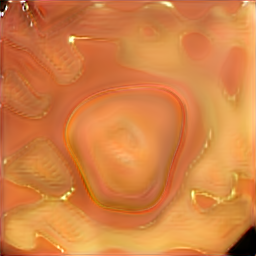

A few sample images and the corresponding masks of the polyp dataset in HyperKvasir are shown in Fig 2. The polyp images are RGB images. The masks of the polyp images are single-channel images with white () for true pixels, which represent polyp regions, and black () for false pixels, which represent clean colon or background regions. In this dataset, there are different sizes of polyps. The distribution of polyp sizes as a percentage of the full image size is presented in the histogram plot in Fig 3, and we can observe that there are more relatively small polyps compared to larger polyps. Additionally, a subset of this dataset was used to prove that the performance of segmentation models trained with small datasets can be improved using our SinGAN-Seg pipeline, and the whole dataset was used to show the effect of using SinGAN-Seg generated synthetic images instead of a large dataset which has enough data to train segmentation models. In this regard, this dataset was used for two purposes:

After training SinGAN-Seg models, we generated random samples per real image using the input scale , which is the lowest scale that uses a random noise input instead of a re-scaled input image. For more details about these scaling numbers and corresponding output behaviors, please refer to the vanilla SinGAN paper [56]. Three randomly selected training images and the corresponding first synthetic images generated using scale are depicted in Fig 4. The first column of the figure represents the real images and the ground truth mask annotated from experts. The rest of the columns represent randomly generated synthetic images and the corresponding generated mask.